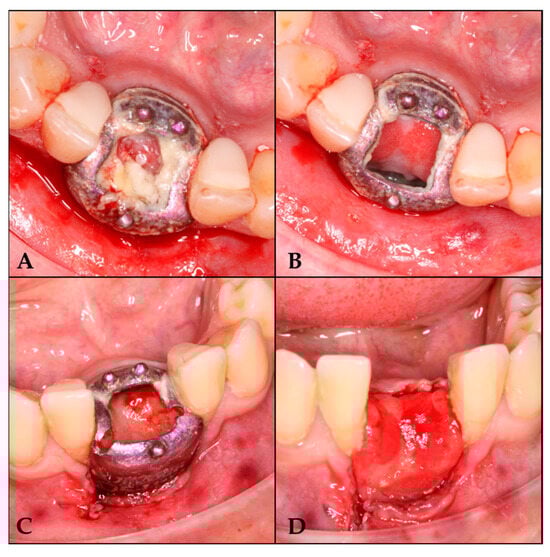

Closure was achieved through a combination of interrupted 3-0 non-absorbable sutures and approximation sutures at the crestal incision. The releasing incisions were subsequently sutured (Figure 2 and Figure 3A), completing the surgical procedure.

Figure 2. Preparation of the area for GBR with the barrier. (A) Area for barrier placement. (B) Full-thickness flap elevation. (C) Barrier fixation with screws. (D) Area for introducing the clot with tricalcium phosphate. (E) Suture of the releasing incision.

Figure 3. Follow-up sequence. (A) 7 days after surgery; (B) 16 days after surgery; (C) 25 days after surgery; (D) 42 days after surgery, once de-epithelialized and with tricalcium phosphate.